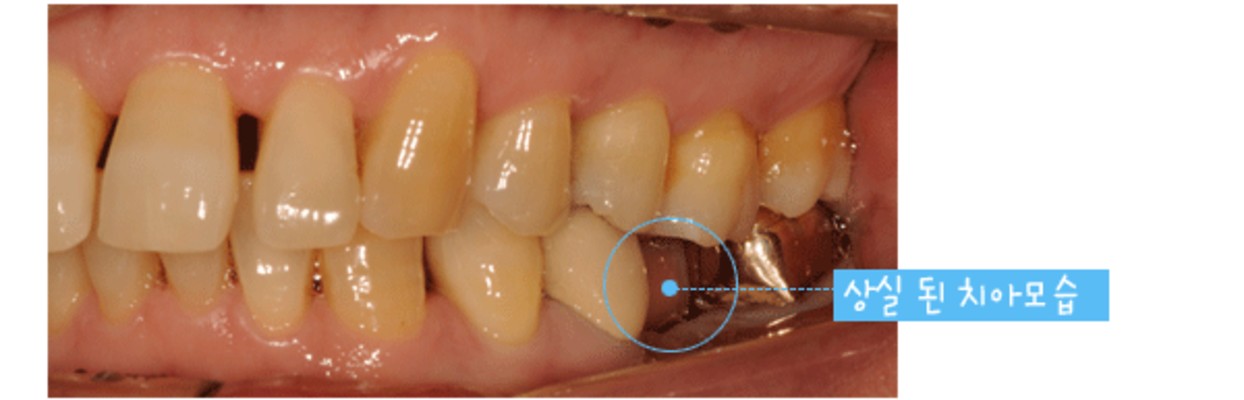

치아 중 어금니는 음식물을 섭취할 때 잘게 부수어 소화가 잘 되도록 돕는 치아입니다. 그러나 음식물을 섭취할 때 음식물 찌꺼기가 남거나 칫솔이 잘 닿지 않는 부위로 충치 발생이 잦은 부위이기도 한데요. 어금니는 충치가 생기기 쉬운 치아로 손실 및 상실로 인한 임플란트 관리를 많이 하는 부위이기도 합니다.

치주질병이나 잇몸 염이 자주 발생할 수 있어 잇몸 관리와 병행하는 사례도 많은 편이죠. 이처럼 어금니가 소실되면 정상적인 저작 기능이 힘들어 식사하는데 매우 큰 불편함을 느낄 수 있습니다. 이 경우 임플란트를 통해 자연 치아에 가까운 씹는 힘과 형태를 되찾을 수 있으며 저작 능력이 강조되는 어금니를 대체하는데 있어 어금니임플란트는 가장 효율적인 관리라고 볼 수 있습니다.